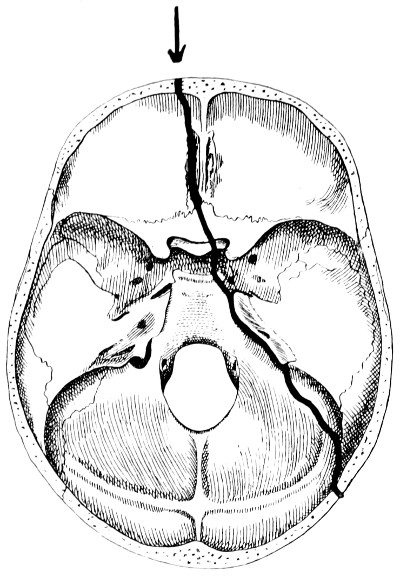

50 A and B. The inner aspect of the skull and the same seen on transillumination 137

51. To illustrate compression of the brain as produced by an extra-dural hæmorrhage from the middle meningeal artery[x] 141